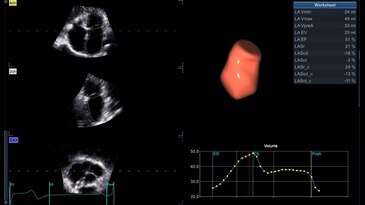

4D Auto LAQ

Данный полуавтоматический алгоритм реконструкции поверхности позволяет проводить быструю, воспроизводимую и точную количественную оценку левого предсердия в 4D-режиме с применением трансторакального датчика для 4D-визуализации. Это обеспечивает расчет объема левого предсердия, а также фракции выброса, общей продольной и круговой деформации.